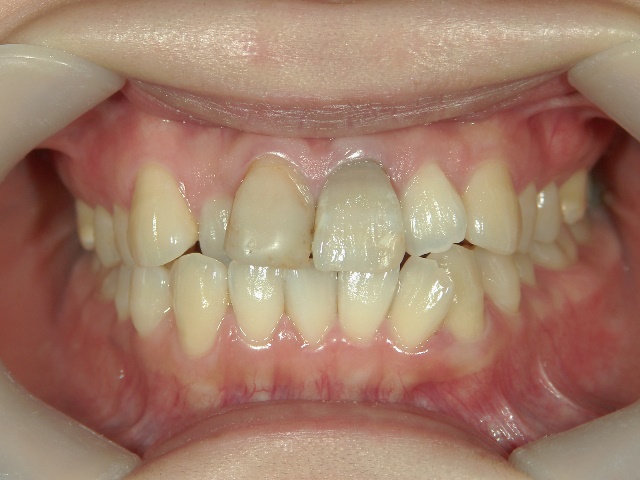

矯正歯科 治療前矯正歯科 治療前

矯正歯科 治療後矯正歯科 プチワイヤー矯正 治療後矯正歯科(プチワイヤー矯正)治療後

プチワイヤー矯正 症例(20

26歳女性 浜松市西区在住

治療期間 1年4カ月

矯正歯科 治療後  スペース確保の為、 2番抜歯